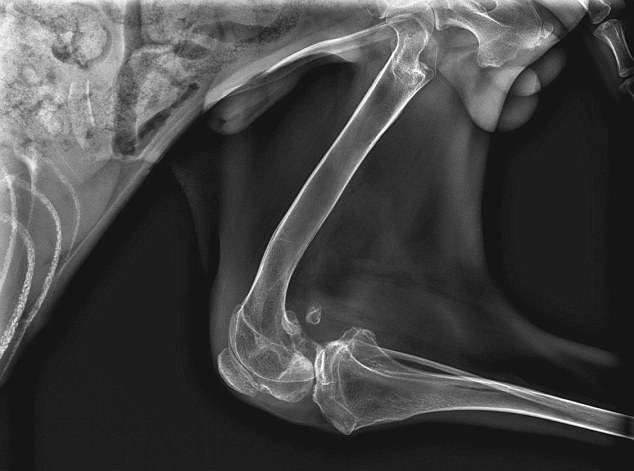

Un cucciolo è stato ritrovato in una condizione davvero terribile. Le zampe dell’animale infatti si sono deformate in maniera grave dopo che il poveretto era stato rinchiuso in una piccola gabbia per mesi. Ora Ping, questo il suo nome, sta cercando una nuova casa e tanto amore. Ha 9 mesi e purtroppo va incontro a tante difficoltà nel camminare perché le sue zampe non sono riuscite a formarsi correttamente mentre cresceva. I veterinari ritengono che sin dalla nascita debba essere stato sottoposto ad una situazione di reclusione in uno spazio strettissimo, senza mai essere stato condotto all’esterno. Come se non bastasse, al momento del suo ritrovamento il cane maltrattato versava in una grave situazione di malnutrizione. A trarlo in salvo sono stati gli animalisti del rifugio ‘Wags 2 Wishes’ di stanza a Chicago. Tutto è avvenuto lo scorso 1° maggio.

Terri Crotty, 46 anni, la fondatrice del rifugio, ha detto che Ping – un meticcio Border Collie/Labrador – è riluttante a usare le zampe posteriori perché avverte tanto dolore. Il cane maltrattato non può camminare sulle sue zampe perché ossa e muscoli non lo reggono come dovrebbero. Ma nonostante la sua difficile educazione, il rifugio sta lavorando per aiutare Ping a raggiungere una situazione di maggiore mobilità. Attualmente alle zampe posteriori sono stati applicati dei supporti per cominciare a far abituare il cucciolo agli spostamenti. Ma lo si sta incoraggiando a camminare anche senza. Terri intanto si dice sicura che l’animaletto troverà presto una famiglia amorevole disposta ad adottarlo. Per Ping, usare le sue zampe posteriori è estremamente doloroso. Stiamo provando però ad aggiustare la sua corporatura”.